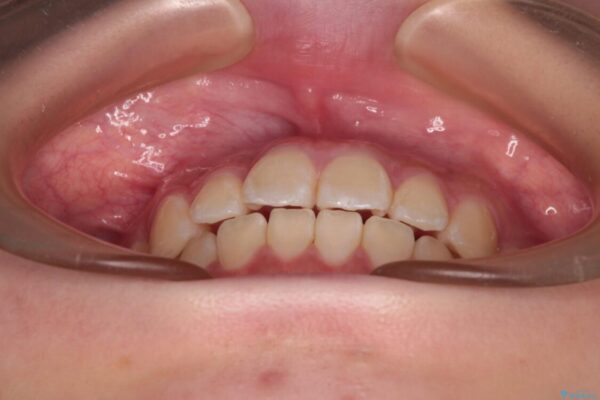

治療前

• インビザラインは使える自信がない ワイヤー装置にて矯正治療 治療前画像